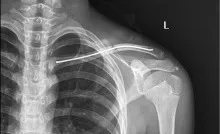

经查体,左肩部可见组织肿胀畸形,可触及左锁骨中端骨折断端阶梯感,压痛明显,纵向叩击痛,左肩关节功能障碍,且家属有手术意愿,为其完善DR拍片、抽血检验等相关术前检查,排除手术禁忌症,经内科、麻醉科等科室会诊后,均认为可择期行手术治疗。手术过程中,医护人员密切配合,麻醉师准确控制麻醉药物的剂量和速度,确保患者在无痛的状态下接受手术。医师团队则凭借精湛的技术和丰富的经验,成功完成了骨折复位内固定手术。

术后拍片

手术后,患者恢复情况良好,疼痛明显减轻,活动能力逐渐恢复。患者对手术效果非常满意,表示八一医院能够提供如此高水平的医疗服务,让他们感到非常的欣慰。